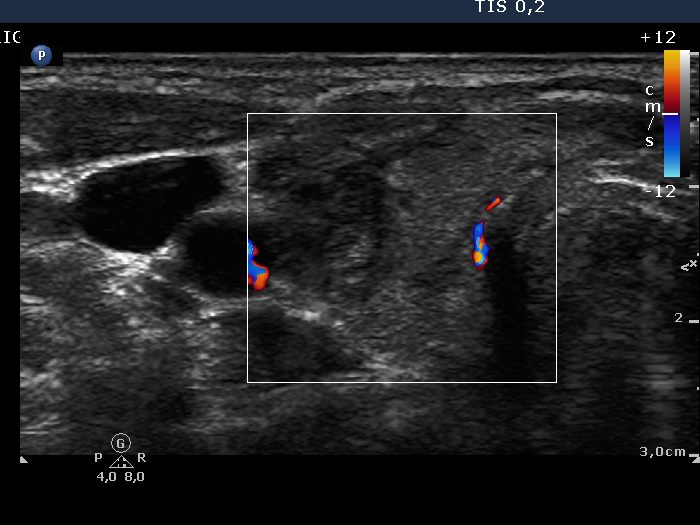

Chronic lymphocytic thyroiditis - Case 1. |

Ultrasonography: the thyroid contained around 40% hypoechogenic discrete lesions. The irregular shape of the lesions and the lack of thyroid enlargement stood for autoimmune thyroid disease, and for Hashimoto's thyroiditis. The presence of nodules in pathological sense was unlikely, but we could not exclude this possibility. The vascularization of the thyroid was decreased. The circumscribed lesion in the right side of the isthmus was aspirated.

The ultrasound pattern (the gray scale mode) disclosed autoimmune thyroid disease with great probability. The decreased vascularization in non-nodular form of hyperthyroidism stands against active hormone-producing disease, but argues for hashitoxicosis with great probability.